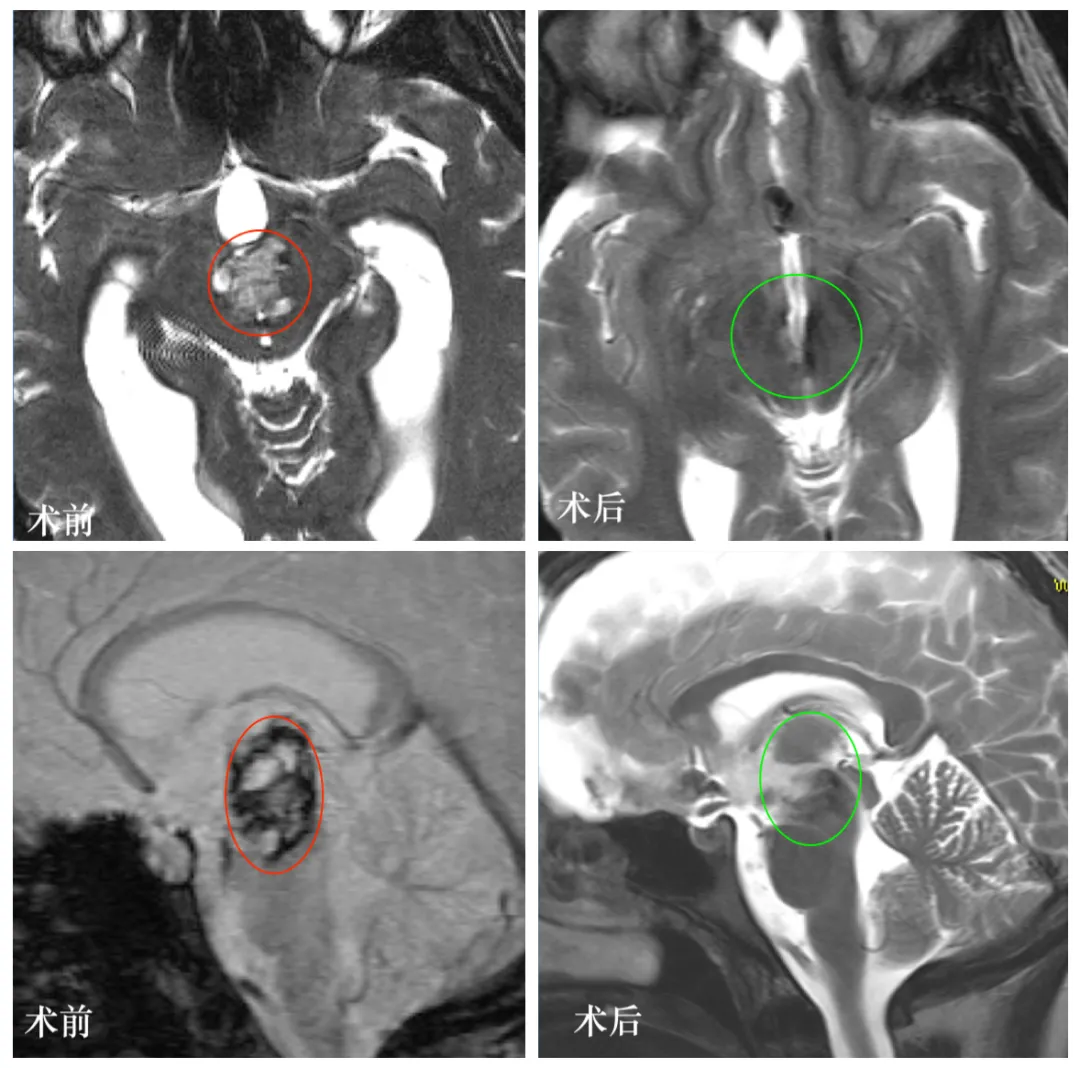

图:Luna的颅脑MR显示中脑巨大占位,混杂信号,海绵状血管瘤可能。

术后当晚,Luna在ICU中苏醒,气管插管顺利拔除,自主呼吸平稳。次日复查MRI:病灶消失,无新发出血或缺血灶。术后第三天,她在康复师协助下下床行走;术后第十四天,拆线出院。

术后两年随访,Luna已顺利完成本科学业,回归正常生活,MRI未见任何复发迹象。